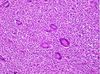

What is this lesion?

Clear Cell Chondrosarcoma ## Footnote Lobulated growth pattern, tumor cells have distinct cytoplasmic boundaries, central nucleus with prominent nucleolus, clear cytoplasm. Trabeculae of woven bone commonly present. 50% of tumors contain nodules of conventional chondrosarcoma